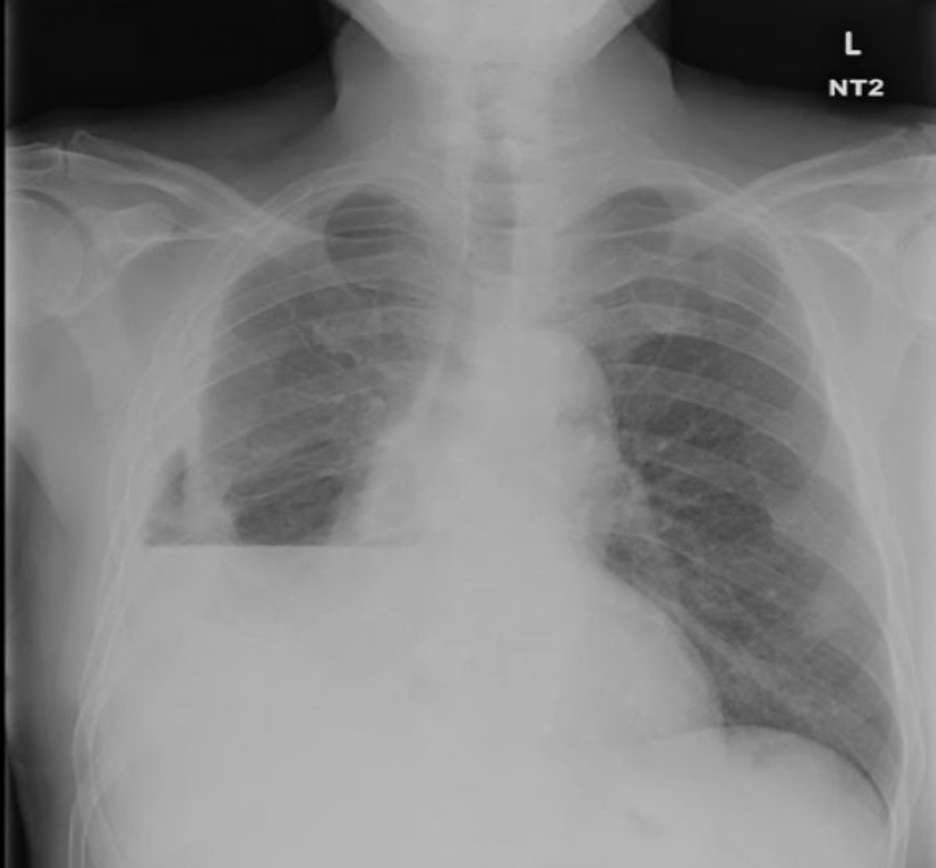

14/Imaging of trapped lung will typically show pleural thickening and loculation. An air contrasted CT can be used to better visualize the visceral pleura rind or you can use direct visualization with video-assisted thoracoscopy. @ReenaHem @ERitterMD @VCURadRes @MarkZieglerMD